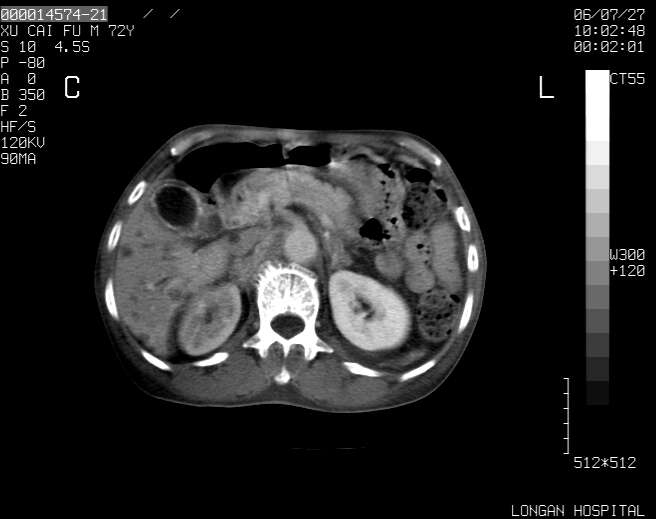

以下是引用winter在2006-7-30 20:14:00的发言:[br]1、考虑胆囊癌伴胆道侵犯并高位胆道梗阻、肝内多发转移、腹膜后淋巴结转移。[br]2、右肾轻度积水。[br]3、老人家72岁了胰腺头体尾部均较饱满,不过未见密度异常及其他异常征象。[br]4、腹水。

以下是引用jiajie在2006-7-31 7:10:00的发言:[br]考虑肝转移瘤,腹膜后淋巴结增大。[br]胃癌不能除外,建议胃镜检查。